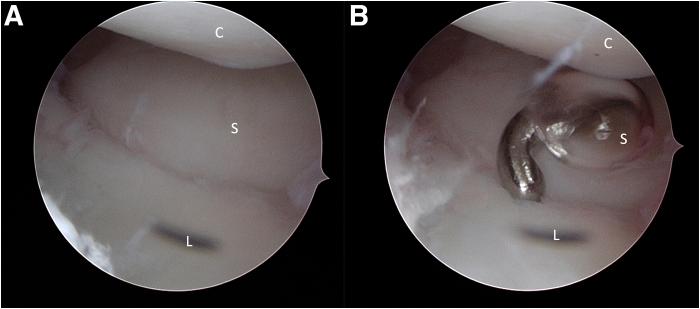

The scapholunate complex is composed of the intrinsic scapholunate ligament and the surrounding extrinsic ligamentous system on the dorsal and volar sides of the wrist. In chronic severe but reducible scapholunate instability (European Wrist Arthroscopy Society stage 4) without arthritis, intrinsic as well as extrinsic ligamentous stabilization becomes highly insufficient and lax. A modification of existing arthroscopic volar capsuloligamentous repair techniques is presented to specifically tighten the volar intrinsic scapholunate ligament in combination with the volar extrinsic scapholunate ligaments, without bone tunnels, bone anchors, or tendon grafts. This technique may be a useful complement to a dorsal extrinsic capsuloligamentous plication in high-grade scapholunate instability.

舟月复合体由腕关节背侧和掌侧的舟月固有韧带及周围的外在韧带系统组成。在无关节炎的慢性严重但可复位的舟月不稳定(欧洲腕关节镜学会4期)中,固有和外在韧带稳定作用变得非常不足且松弛。本文介绍了一种对现有关节镜下掌侧关节囊韧带修复技术的改良方法,该方法无需骨隧道、骨锚或肌腱移植,专门收紧掌侧舟月固有韧带并结合掌侧舟月外在韧带。该技术可能是对高度舟月不稳定进行背侧外在关节囊韧带折叠术的有用补充。